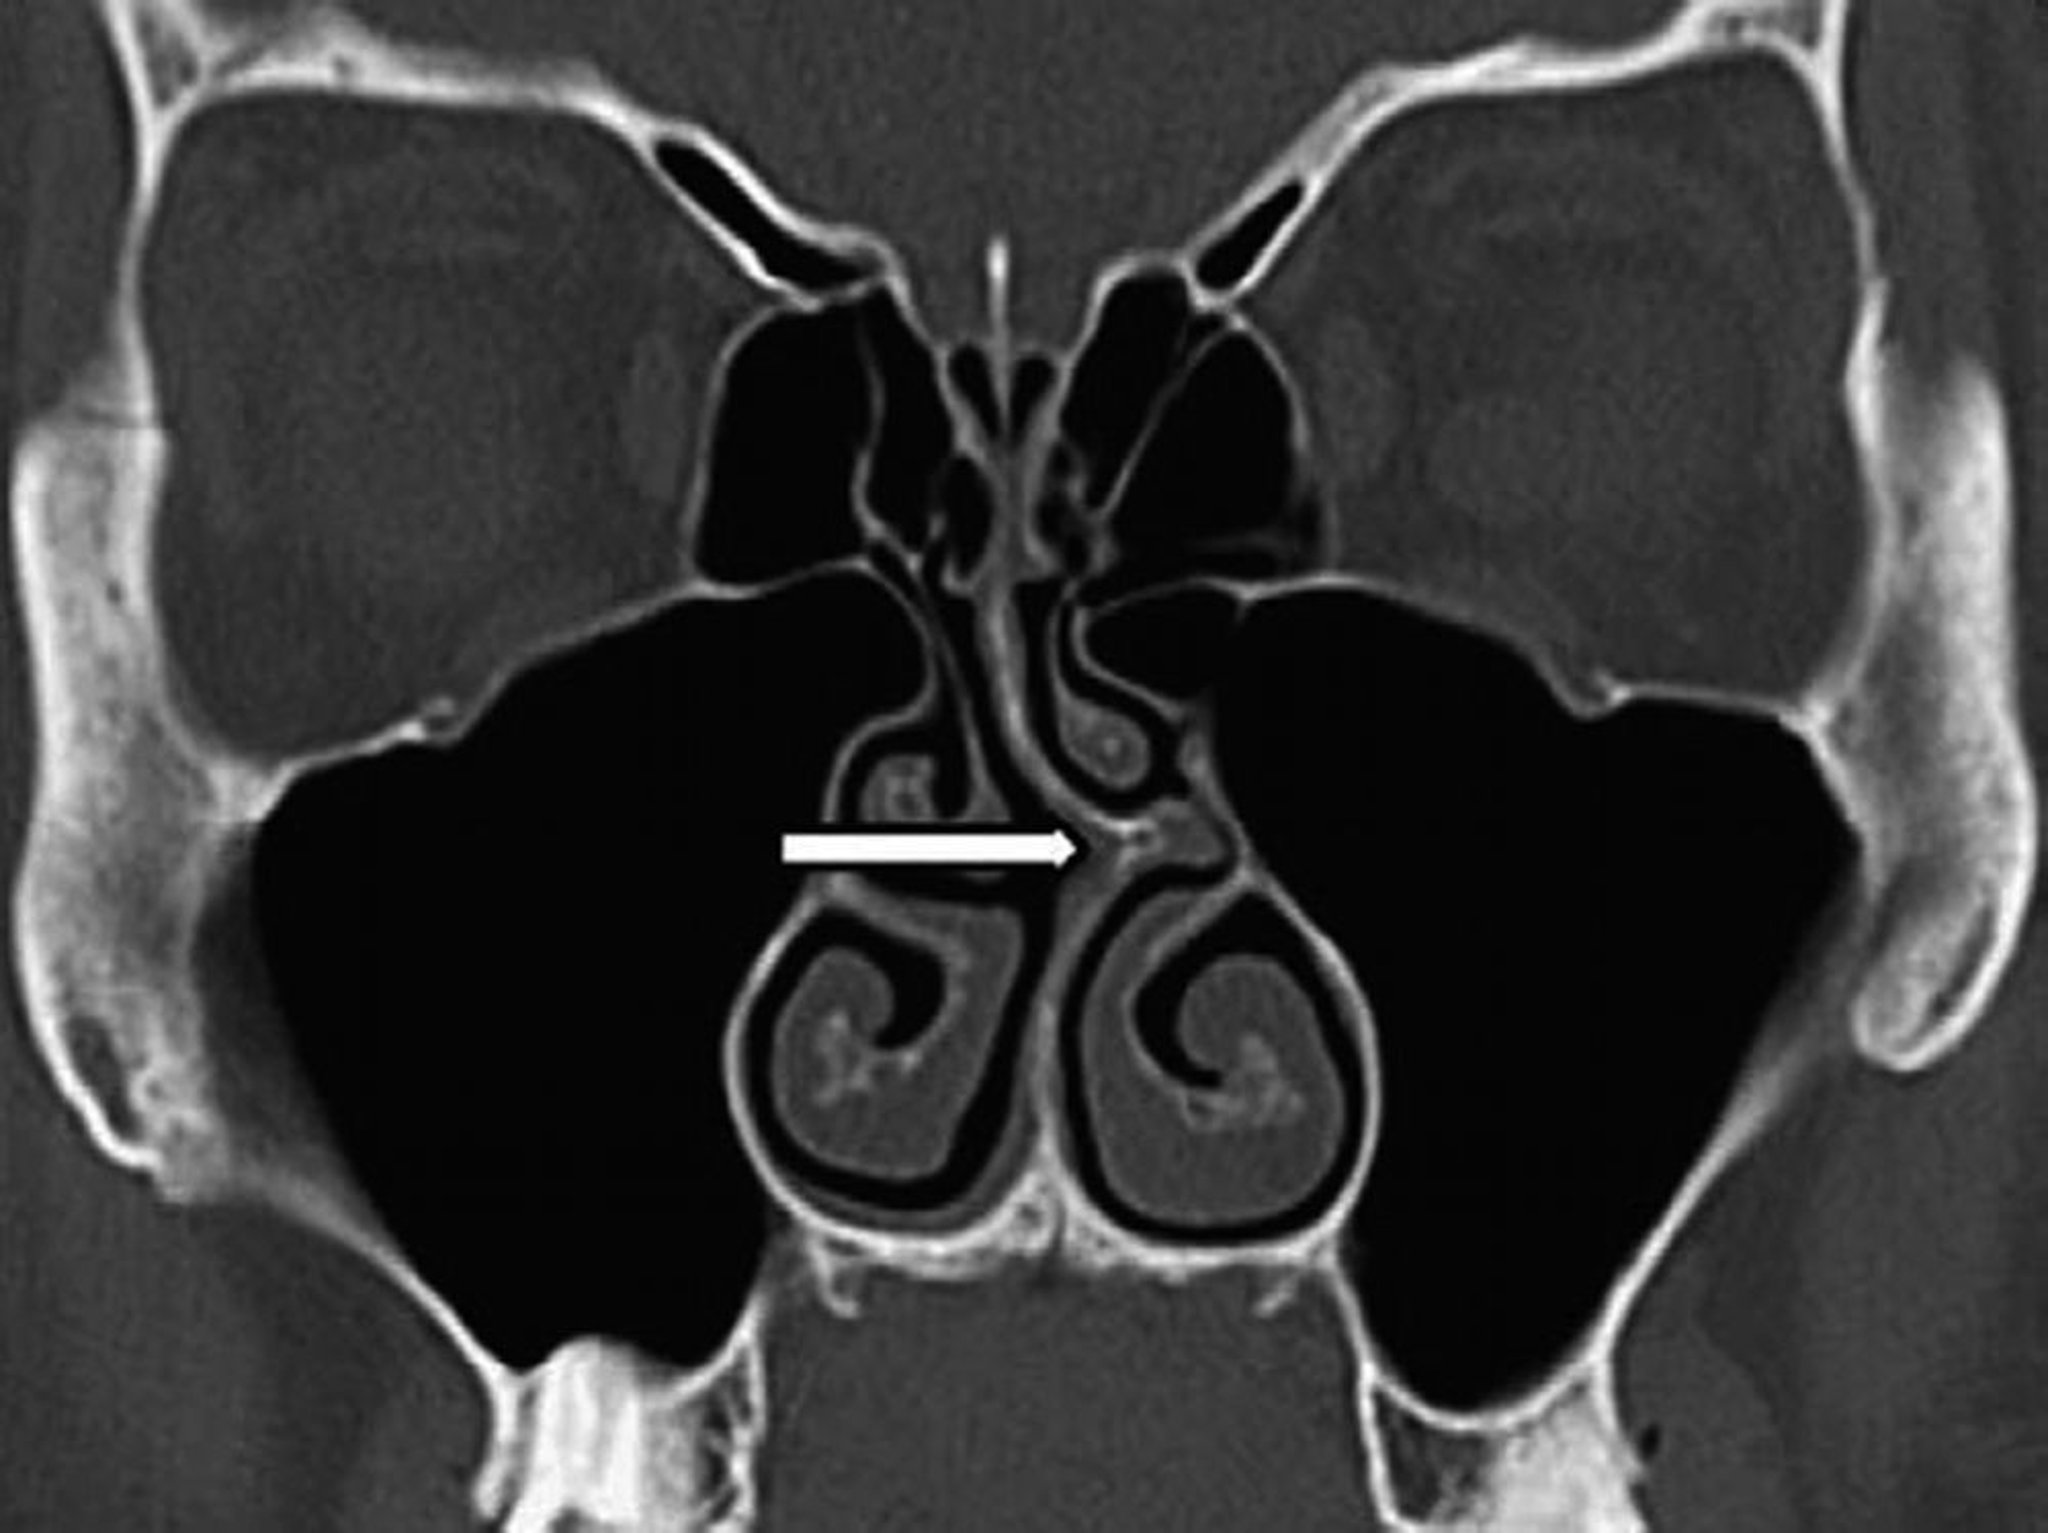

Septal Deviation (CT Scan)

This coronal CT scan shows deviation of the nasal septum to the left (arrow).